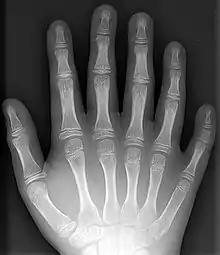

- Polydactyly – additional fingers or toes[6]

- Supernumerary bones – these additional bones are fairly common, particularly in the feet, and are frequently mistaken for fractures on x-rays.

- Syndactyly – webbing between the fingers or toes[6]